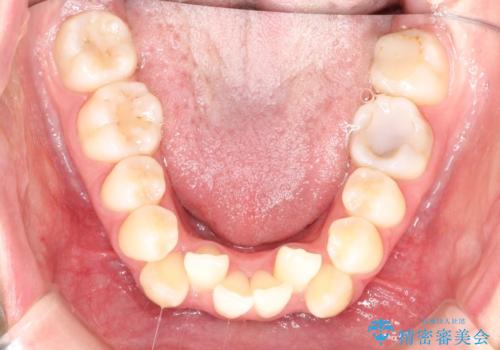

重度のガタガタ ハーフリンガルによる目立たない抜歯矯正

- 八重歯と前歯のガタガタを主訴に来院されました。

目立たない装置をご希望でしたので、上下左右の歯を1本ずつ抜歯してハーフリンガルでの矯正を行いました。